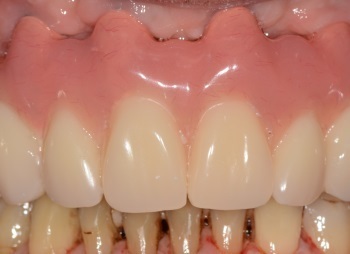

Le bridge provisoire est posé 5 jours après la pose des implants.

Le bridge d’usage est posé 6 mois après le bridge provisoire. L’esthétique et l’entretien du bridge sont optimisés.